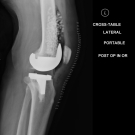

A 73-year-old man with a history of hyperlipidemia, hypertension, diabetes, and degenerative joint disease who had undergone left knee total replacement approximately 3½ years ago presented with a 1-day...

12/05/2019